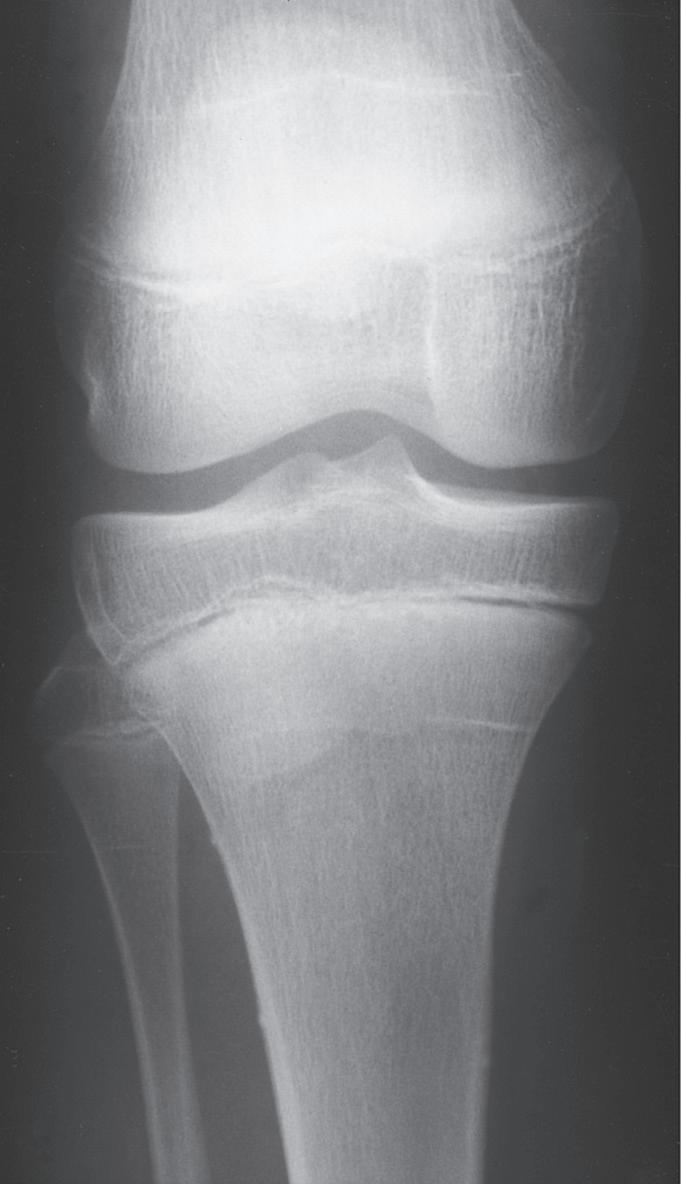

GROWTH ARREST LINES OR GROWTH SLOWDOWN LINES

In radiographs of bones that were fractured several weeks to months previously, transverse lines may be seen in the metaphyseal region. These lines are usually referred to as Harris growth arrest lines, or the transverse lines of Park,60 and are unique to children’s bones after a fracture or injury. These transversely oriented trabeculae occur in bones that are normally growing rapidly (e.g., femur or tibia) and in those in which the trabeculae are predominantly longitudinally oriented (Fig. 1.3). When growth deceleration occurs, as happens immediately after a fracture of an extremity, the bone is, in effect, standing still and making transversely oriented trabeculae. The calcified cartilage and bone formed has increased density and is evident radiographically after further growth. Arrest lines should parallel the physeal contour if the physis is growing normally. After a fracture, these lines are typically visible 6 to 12 weeks after injury and can provide the orthopedist with the ability to assess and predict abnormal growth.60 A specific effort should be made to look for these arrest lines during radiographic evaluation of childhood fractures, especially those involving the physes, because lines that do not parallel the physis indicate an area of physeal damage or an osseous bridge.60,61 Arrest lines that do not parallel the physis point to an area of abnormal physeal growth.

The physes that grow more rapidly (e.g., the distal end of the femur or the proximal end of the tibia) have arrest lines farthest from the physis. In the metaphyseal areas of bones, where the slowest growth occurs, transverse trabeculae may be difficult to see radiographically or may not form at all.

Transversely oriented Harris lines may also result from any type of stress on the bone that causes a temporary slowdown in the formation of longitudinally oriented bone. Such stresses include systemic illness, fever, and starvation,

Fig. 1.3 Anteroposterior (A) and lateral (B) radiographs of the knee of a 12-year-old child 6 months after a femoral shaft fracture. Arrest lines parallel to the physis can be seen in the metaphyseal area of the distal end of the femur and proximal tibia (arrows). The temporary depression of growth at the time of injury results in more horizontal trabeculae being laid down, thereby increasing the density of bone at that level.

as well as skeletal trauma.62 Similar lines can be seen in skeletally immature patients being treated with bisphosphonates, and are called zebra lines in osteogenesis imperfecta patients.63,64